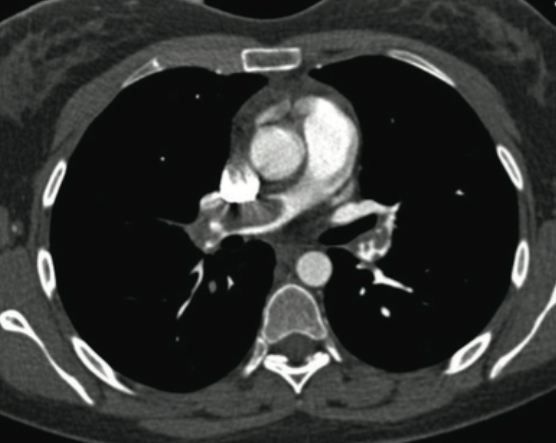

55yo female with known breast cancer develops sudden onset dyspnoea associated with pleuritic chest pain. On questioning she admits to having unilateral calf pain prior to this

PE